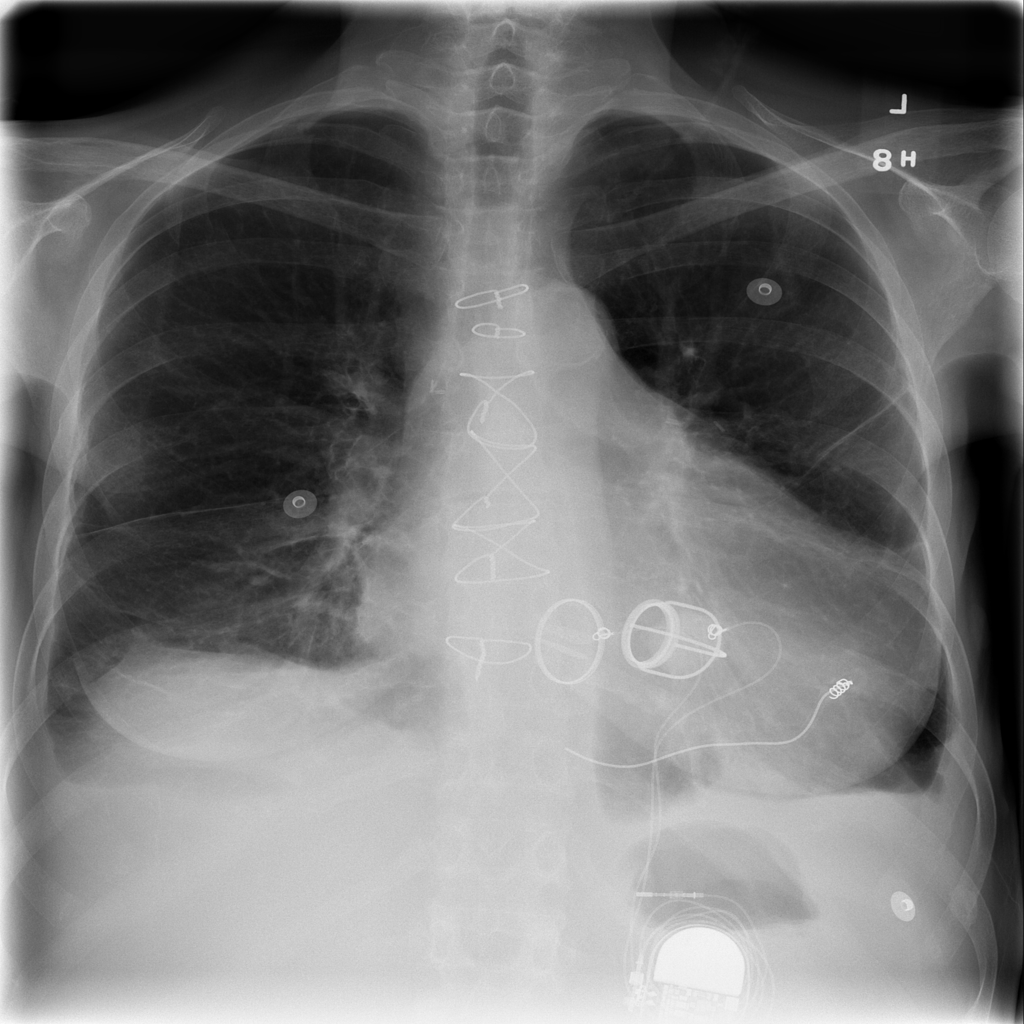

PAT-40F9 · IMG-004Effusion

PAT-40F9 · IMG-004

PA